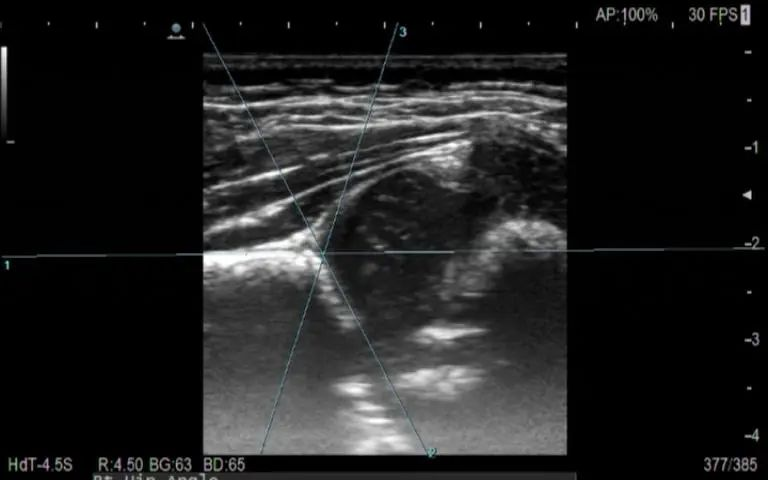

图一:膝关节半月板损伤

图二:腕管综合症